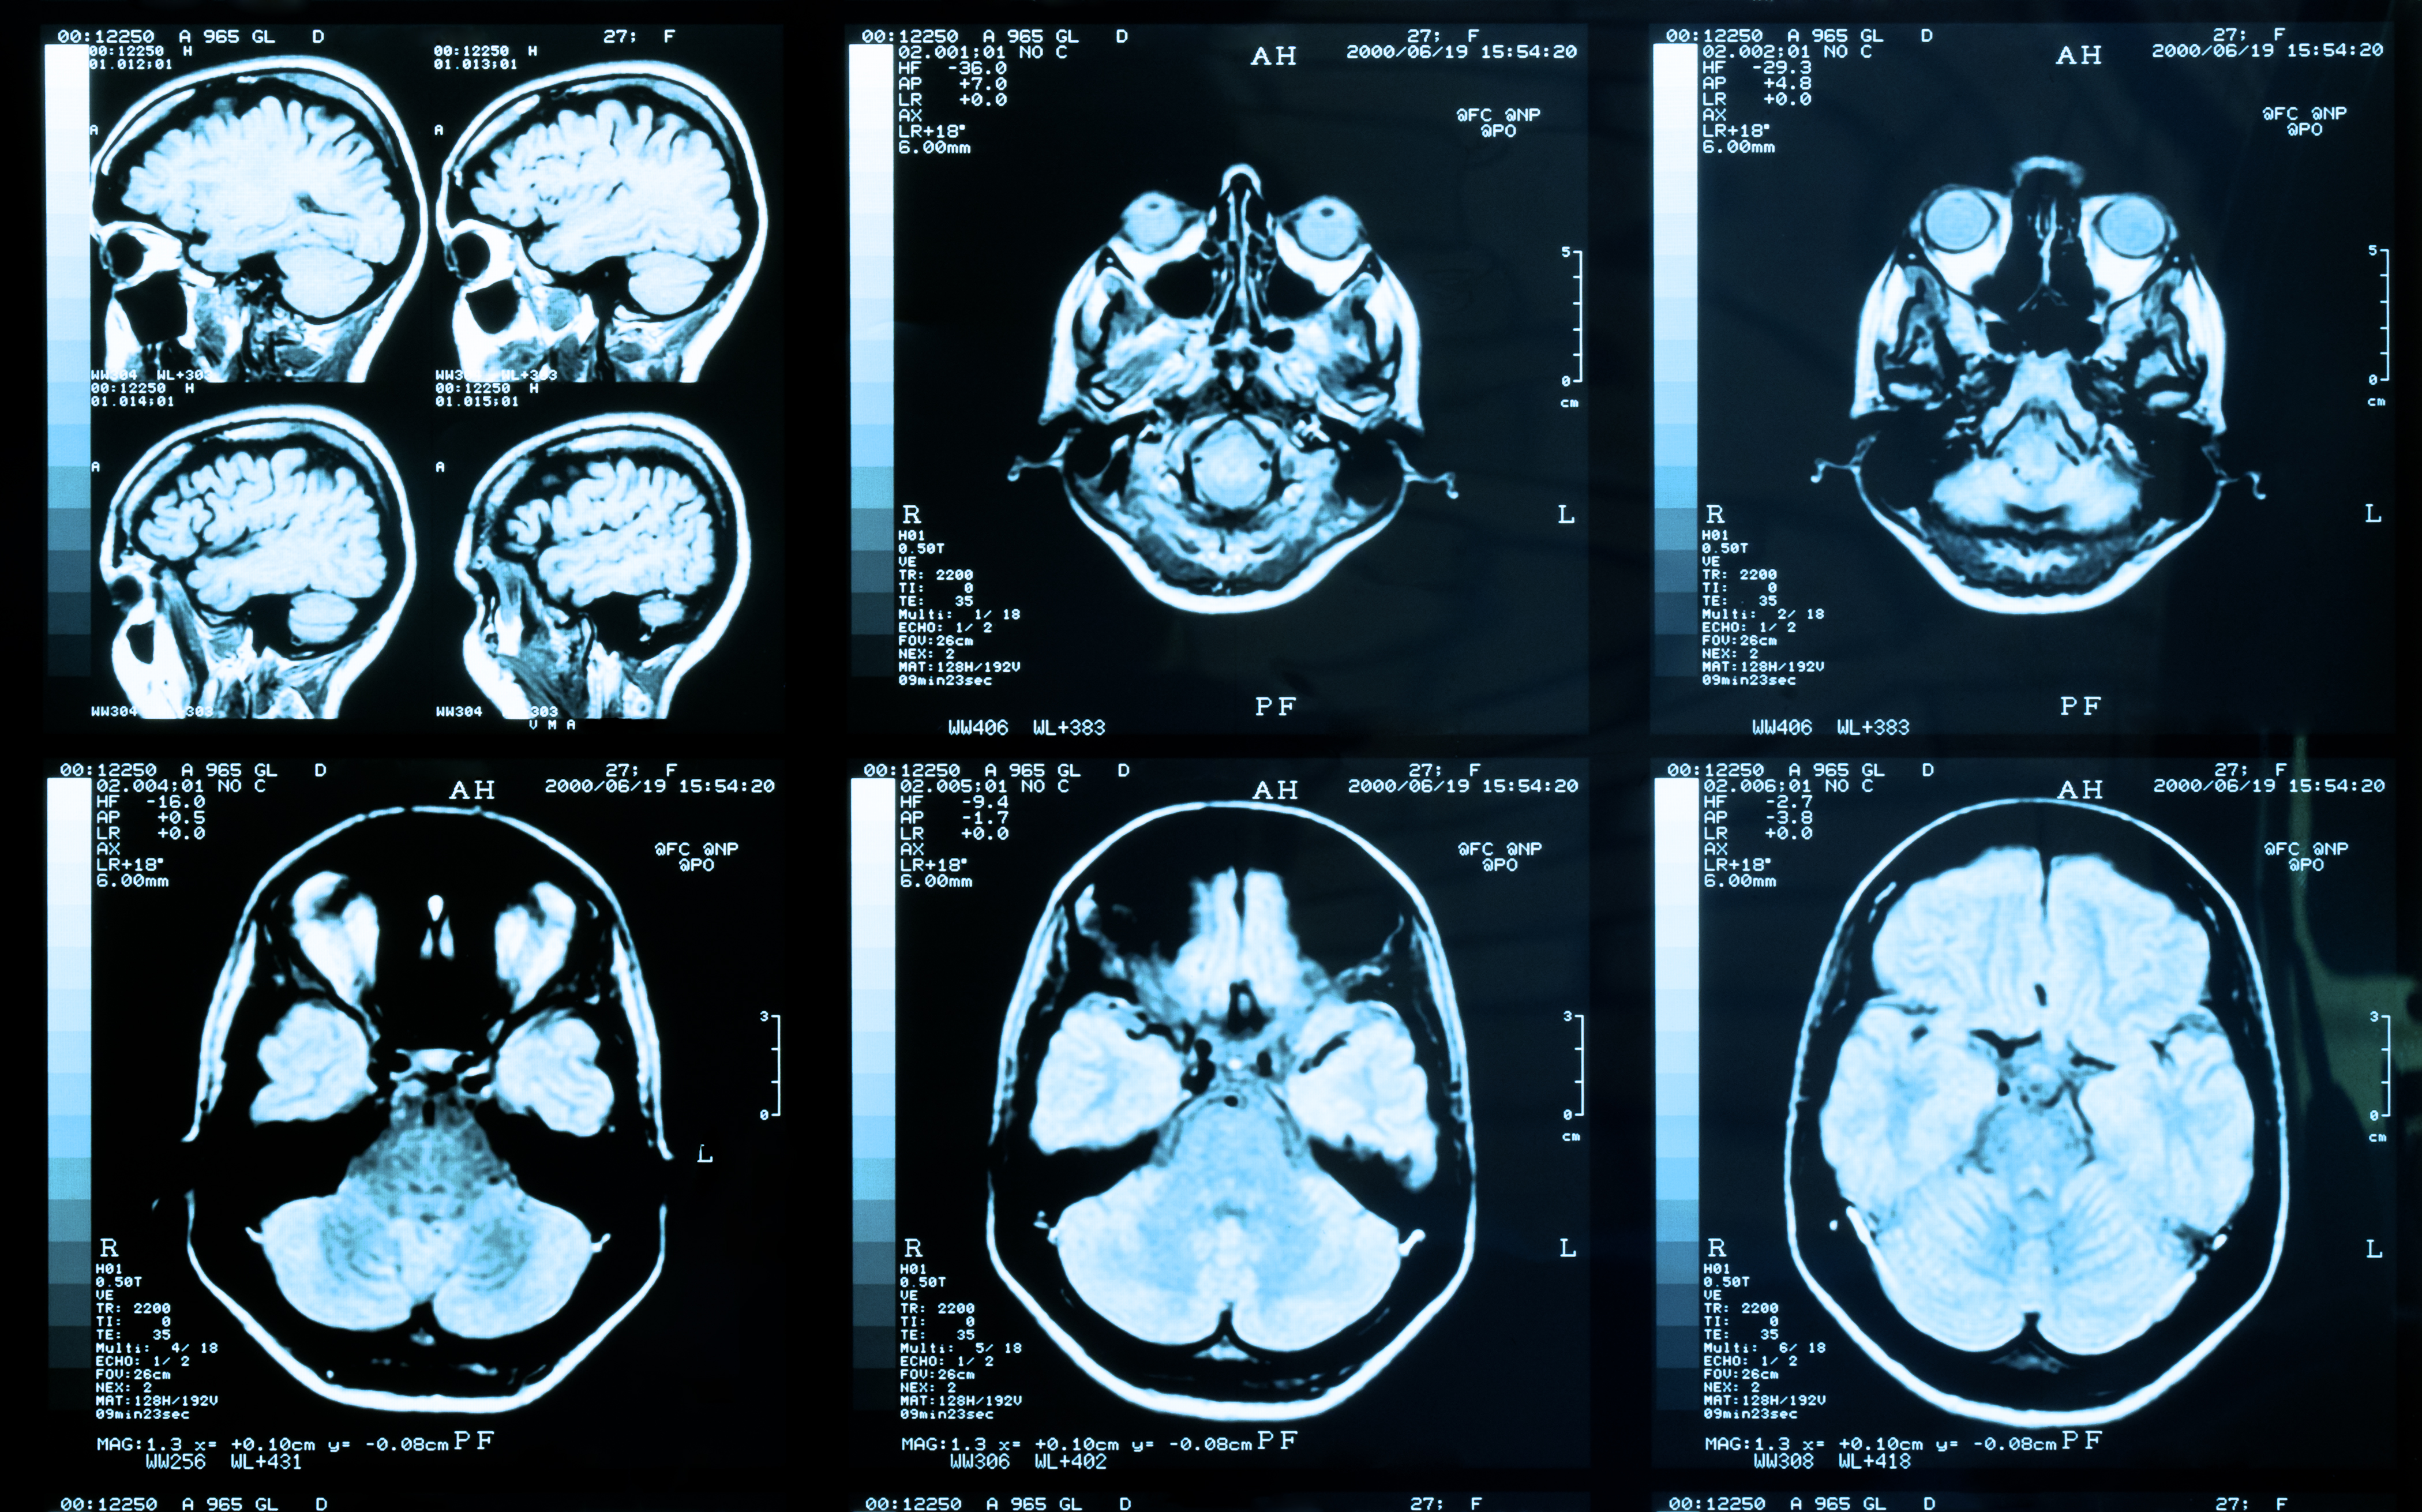

B-SNIP’s starting point was to take approaching 1000 patients with 1 of 3 conventional diagnoses – schizophrenia, schizoaffective disorder and psychotic bipolar disorder – and measure a wide range of cognitive variables, electrophysiological variables such as auditory evoked potentials, and aspects of eye movement, along with structural and functional MRI.

Though essentially a treatment study, OPTiMiSE, which included 481 patients aged 18-40 with untreated symptoms for less than two years and less than two weeks’ lifetime exposure to antipsychotics,3 had a functional MRI component.

The 201 patients studied had a baseline, pre-treatment MRI. This was assessed in relation to outcome at four weeks, using PANSS criteria, at which point 68% of patients in this subset were considered to be in remission. Various structural brain measures were used, notably mean cortical thickness in 31 regions, surface area and a local gyrification index of cortical folding. There were also measures relating to subcortical regions. The bottom line is that none of these baseline MRI measures predicted clinical outcome.

Perhaps, Dr Lawrence speculated, four weeks is too short to assess any correlation. Perhaps the study was compromised by heterogeneity in imaging and assessment between the many sites involved. Or perhaps brain structure is simply not that a good predictor, and other imaging modalities – or different biomarkers entirely, such as those relating to inflammation -- would give us a better handle on processes underlying the disease and its response.